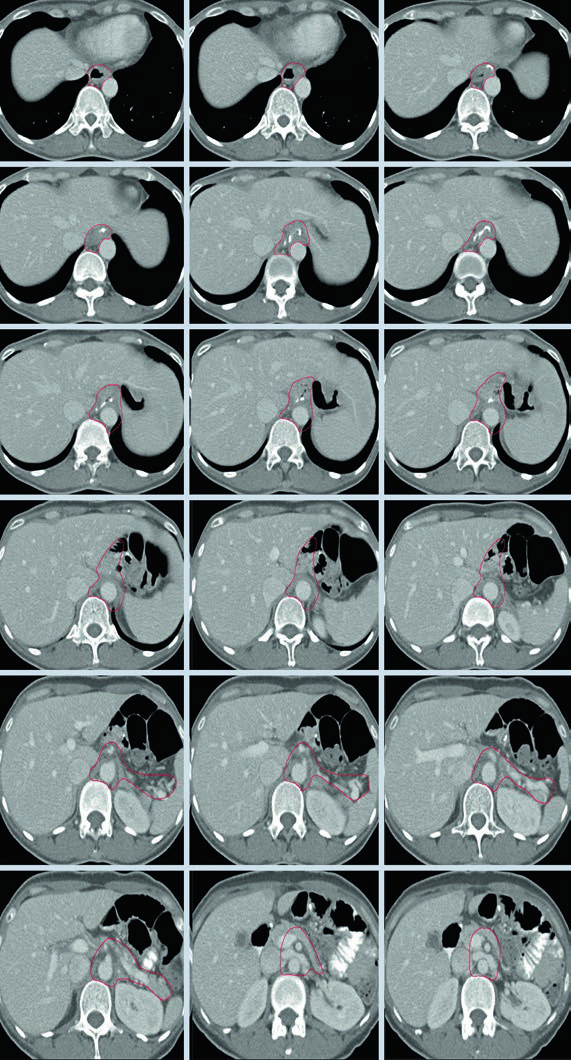

Caso 1: T1N1M0 Adenocarcinoma da Cárdia — Gastrectomia Total

Neste caso, o CTV engloba a anastomose esofagojejunal, o ligamento hepatogástrico, a artéria celíaca e o hilo esplênico. Como se trata de gastrectomia total em tumor da cárdia com linfonodo positivo, não há remanescente gástrico a incluir, mas os volumes nodais devem ser amplos.

Caso 2: T3N3M0 Adenocarcinoma do Corpo — Gastrectomia Distal

Com doença T3N3, o CTV é extenso: inclui anastomose gastrojejunal, estômago remanescente, artéria celíaca, hilo esplênico e leito tumoral pancreático. Esse cenário exige atenção especial às restrições de dose nos órgãos de risco — particularmente rins e fígado — pois o volume de tratamento é considerável.

Caso 3: T2N1M0 Adenocarcinoma de Antro/Piloro — Gastrectomia Distal

No adenocarcinoma de antro/piloro, o CTV abrange a anastomose gastrojejunal, o estômago remanescente, o ligamento hepatogástrico e o coto duodenal. A cobertura do hilo esplênico é opcional neste cenário. A inclusão do coto duodenal é preferencial em gastrectomias parciais por tumores distais/antrais, mas não deve ser incluída em pacientes com tumores proximais submetidos a gastrectomia total.